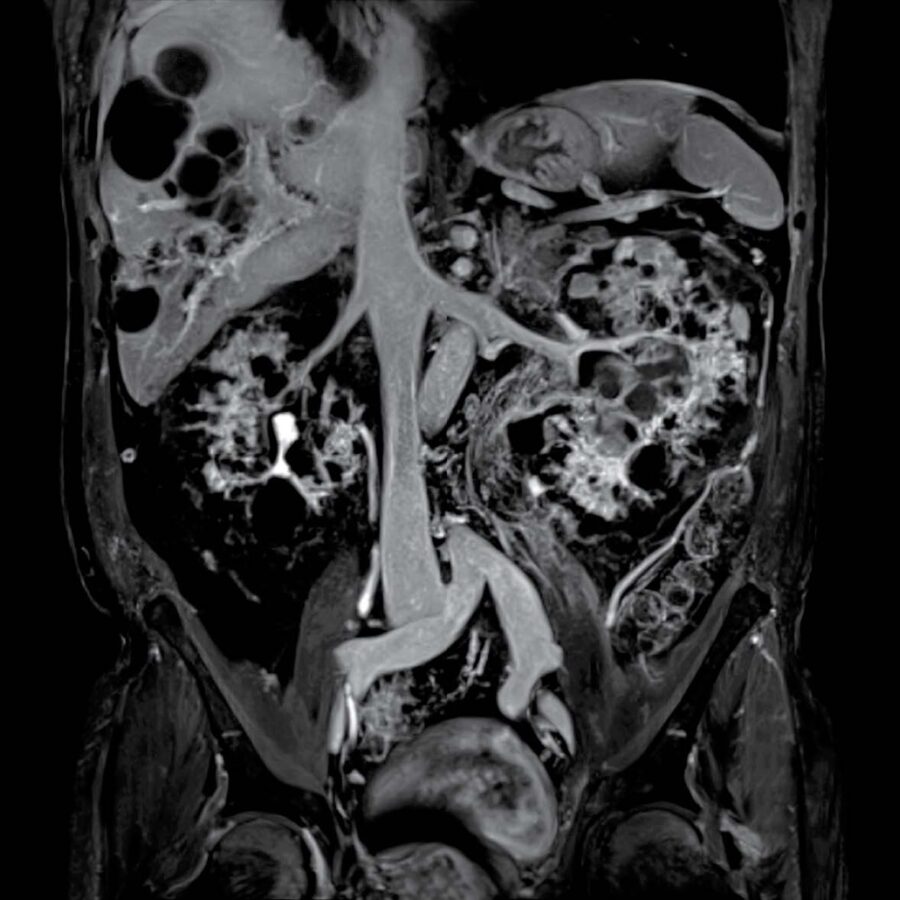

Total Body Imaging

Using 3T MRI technology

Welcome to Kansas City Advanced Diagnostic Imaging Services-Overland Park’s new destination for advanced brain and body imaging. Save time and get the detailed answers you need with our state-of-the-art 3T MRI, featuring 128 channels and a wide bore, which doctors prefer for superior structural detail. We also offer functional imaging for advanced neurological and psychiatric diagnostics. Your scans are interpreted by radiologists with extensive expertise in all imaging modalities. At Kansas City Advanced Imaging, our focus is on providing you with clarity, precision, and peace of mind with every scan.

Our advanced imaging systems provide physicians across specialties with the critical insights needed for effective intervention, surgical planning, and treatment tracking.